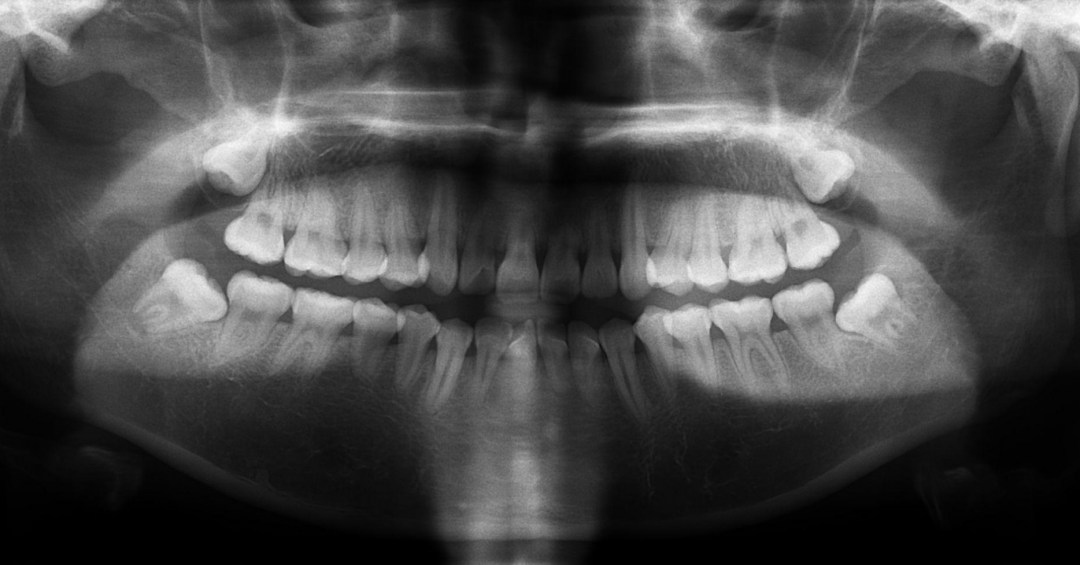

本期内容,我们将通过图文并茂的形式为大家详细讲解X光机的拍摄技术与心得。

上颌后牙X光拍摄的难点的原因分析:

A:我们人体的脸部肌肉密度非常大,颌骨的密度每个人的发达程度也不一样,人的面部侧方轮廓是有直面型,凸面型,凹面型,甚至有不规则型的。即使X光机器上有标准的刻度,但球管对面部的哪个投照体表标志会是更准确点呢?心里却是茫然的。拍摄后牙的厚度,比我们手掌的最厚部位还要厚3分之一呢!

B:牙科胶片固定于上颌后部的舌腭面,很多人咽部较为敏感,轻微的刺激就会恶心,流口水,咽部易感,影响拍摄。如果以上操作不正确,则尤甚,增加患者的痛苦,影响片子的质量!